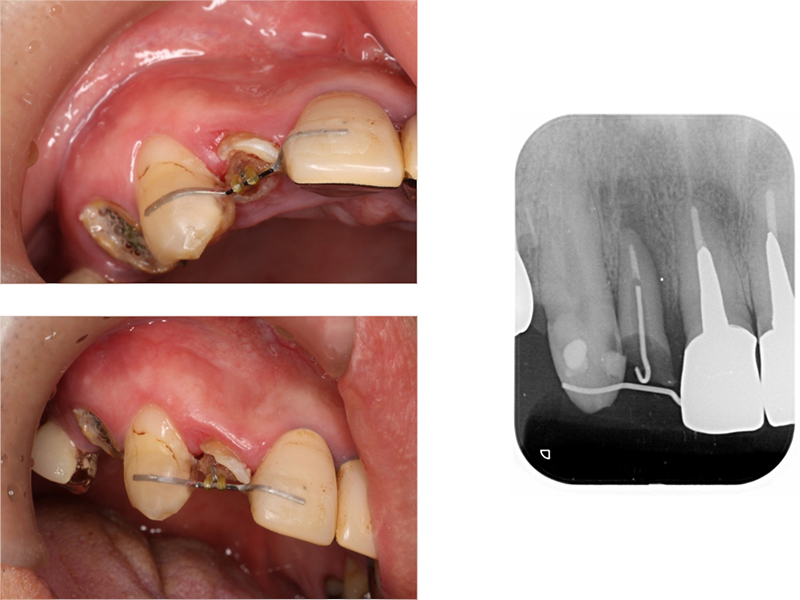

▼ ケース6.矯正的挺出

矯正開始

矯正終了

矯正開始前、矯正終了時、補綴終了